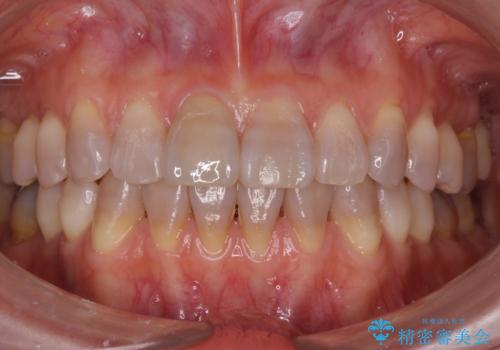

転んで前歯が折れた 色合いの難しい歯のセラミック修復

テトラサイクリン歯といって縞模様の強い歯の色調再現を行いました。

- 16.5万円(内訳:仮歯1万円、ジルコニアクラウン(スペシャル)14万円)費用は治療当時の料金となります

まず保険治療でコンポジットレジン修復を行い、神経の状態を確認した後、クラウンによる修復を行いました。

将来神経が失活する可能性もありますので経過観察する必要があります。